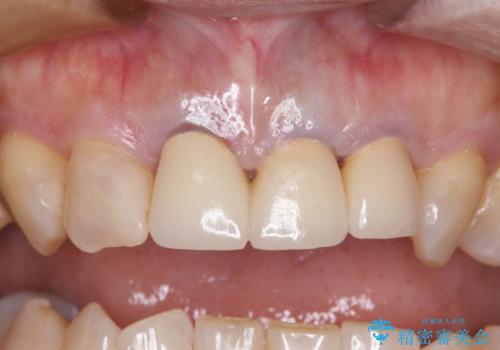

- 黄色みのある前歯のセラミックを、明るい色に替えたいとのことで来院された患者様です。

透明感がないことも気になっていたため、オールセラミッククラウンでは透けてしまう可能性のある金属の土台をファイバーコアに置き換え、1トーン明るいクラウンにて仕上げていくこととしました。

透明感のある自然な色合いとなり、患者様には大変満足していただけました。